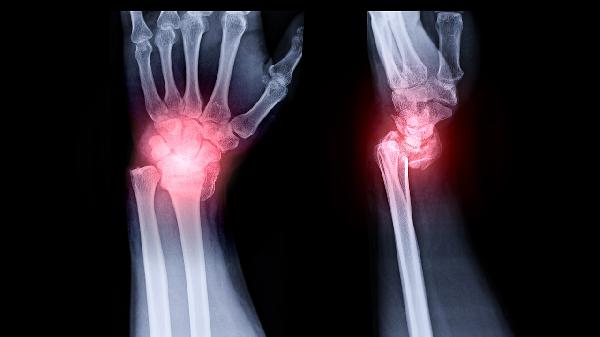

普通骨折多由交通事故、高处坠落等明确外伤导致,骨质结构原本正常,暴力超过骨骼承受极限时发生断裂。骨折线清晰且周围无异常骨改变,常见于四肢长骨如桡骨、胫骨,通常伴随剧烈疼痛、畸形和功能障碍。治疗以复位固定为主,可采用石膏外固定或钛合金接骨板内固定,配合塞来昔布胶囊等药物缓解疼痛,康复期需逐步进行关节活动度训练。